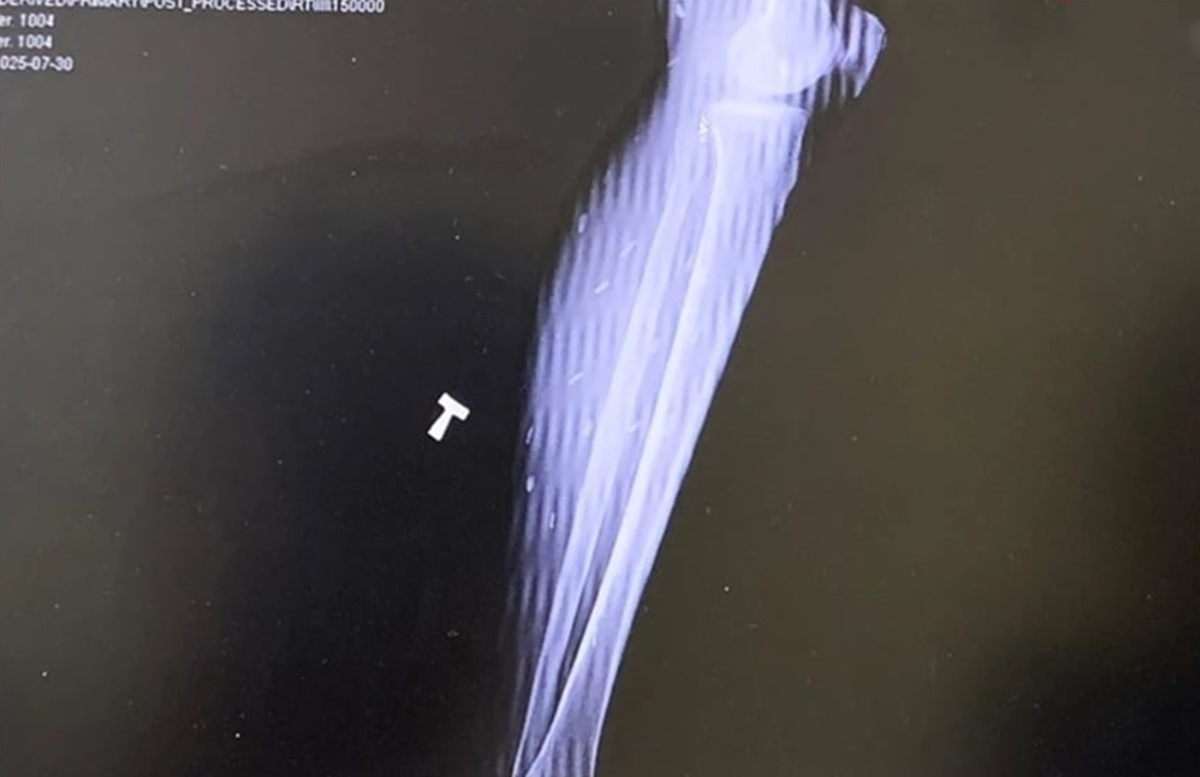

Sán ký sinh trong cơ thể người bệnh. Ảnh: BVCC